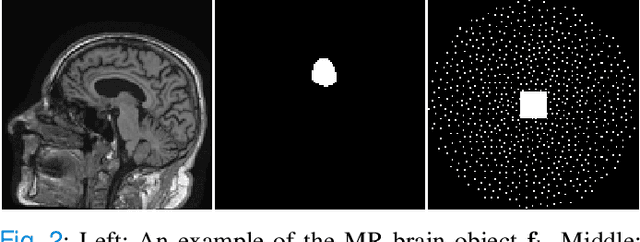

Abstract:In order to objectively assess new medical imaging technologies via computer-simulations, it is important to account for all sources of variability that contribute to image data. One important source of variability that can significantly limit observer performance is associated with the variability in the ensemble of objects to-be-imaged. This source of variability can be described by stochastic object models (SOMs), which are generative models that can be employed to sample from a distribution of to-be-virtually-imaged objects. It is generally desirable to establish SOMs from experimental imaging measurements acquired by use of a well-characterized imaging system, but this task has remained challenging. Deep generative neural networks, such as generative adversarial networks (GANs) hold potential for such tasks. To establish SOMs from imaging measurements, an AmbientGAN has been proposed that augments a GAN with a measurement operator. However, the original AmbientGAN could not immediately benefit from modern training procedures and GAN architectures, which limited its ability to be applied to realistically sized medical image data. To circumvent this, in this work, a modified AmbientGAN training strategy is proposed that is suitable for modern progressive or multi-resolution training approaches such as employed in the Progressive Growing of GANs and Style-based GANs. AmbientGANs established by use of the proposed training procedure are systematically validated in a controlled way by use of computer-simulated measurement data corresponding to a stylized imaging system. Finally, emulated single-coil experimental magnetic resonance imaging data are employed to demonstrate the methods under less stylized conditions.